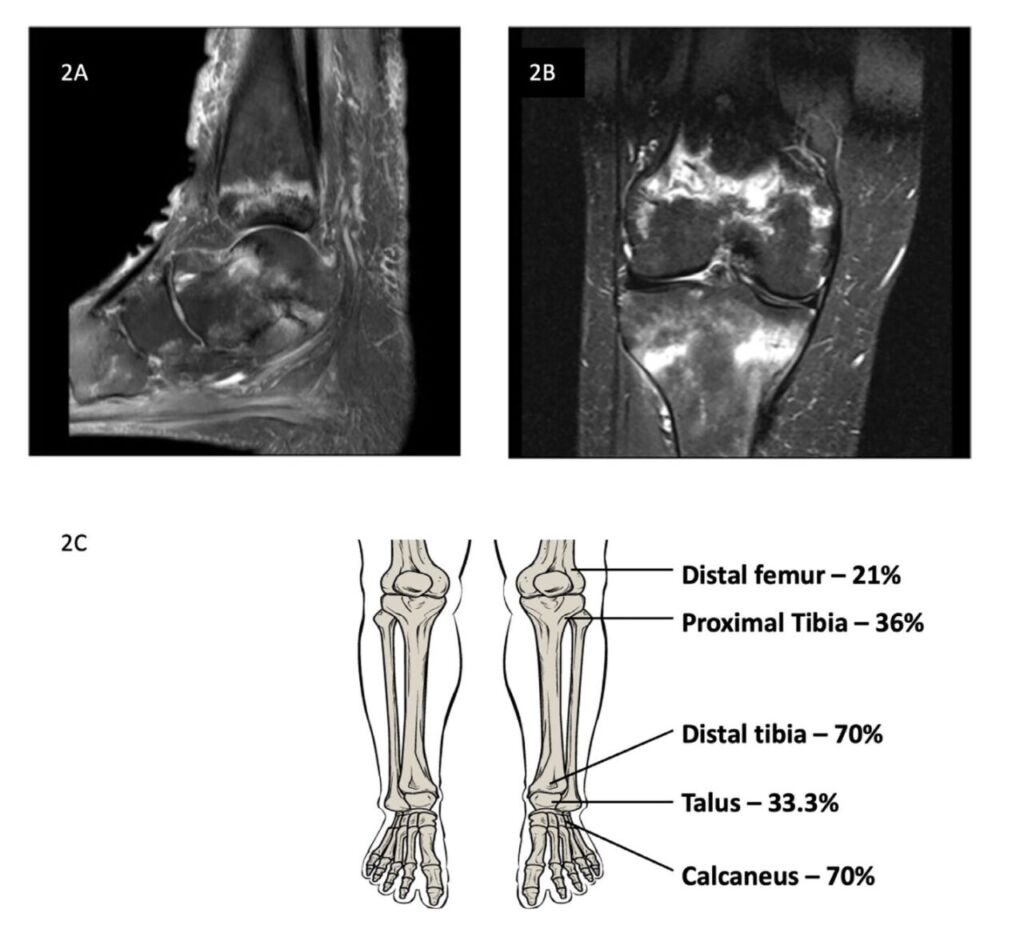

メトトレキサート関連脆弱性骨折(Methotrexate osteopathy: MTXO)は、低用量MTXを長期使用しているリウマチ患者においておきる下肢の骨折として報告されている。骨折のパターンは特徴的で、MRIで帯状または曲線状の不全骨折線を示し、遅れて診断されやすい。

画像を見る限りは脆弱性骨折のようなもので、おそらくMRIを撮らないとわからないものなんでしょう。特徴的な帯状のバンドがでるようです。見たら異常とは気づきますがこれがメトトレキサートによるのだと気づくには知っていなければ無理ですよね・・・でも知っていれば一発診断。こういうのは勉強しておくしかないです。